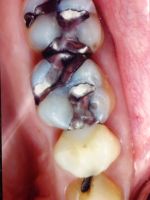

Before

After